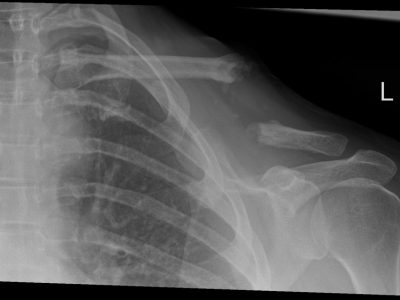

Παρακάτω παρατίθενται ακτινογραφίες καταγμάτων του άνω άκρου που αντιμετωπίζονται με εσωτερική οστεοσύνθεση ή επανορθωτική χειρουργική με αρθροπλαστική.